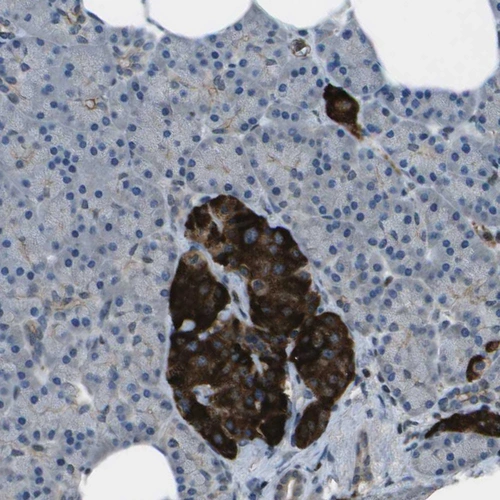

Immunohistochemical staining of human Heart muscle shows moderate cytoplasmic positivity in cardiomyocytes.